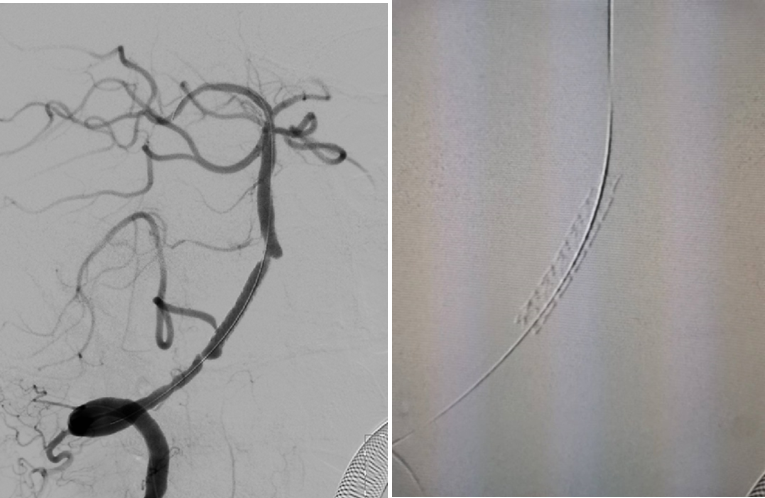

首次DSA 2022.4.9:

导丝怎么扩【载药时代 球扩天下】NOVA DES®颅内药物洗脱支架在椎动脉颅内段重度狭窄的应用二例_https://www.jmylbn.com_新闻资讯_第6张

导丝怎么扩【载药时代 球扩天下】NOVA DES®颅内药物洗脱支架在椎动脉颅内段重度狭窄的应用二例_https://www.jmylbn.com_新闻资讯_第7张

重要影像结论DSA:左侧椎动脉闭塞,右侧椎动脉V4段重度狭窄。